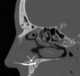

Incisive canal cyst

The nasopalatine duct cyst (NPDC) occurs in the median of the palate, usually anterior to first molars. It often appears between the roots of the maxillary central incisors. [Source: Wikipedia ]